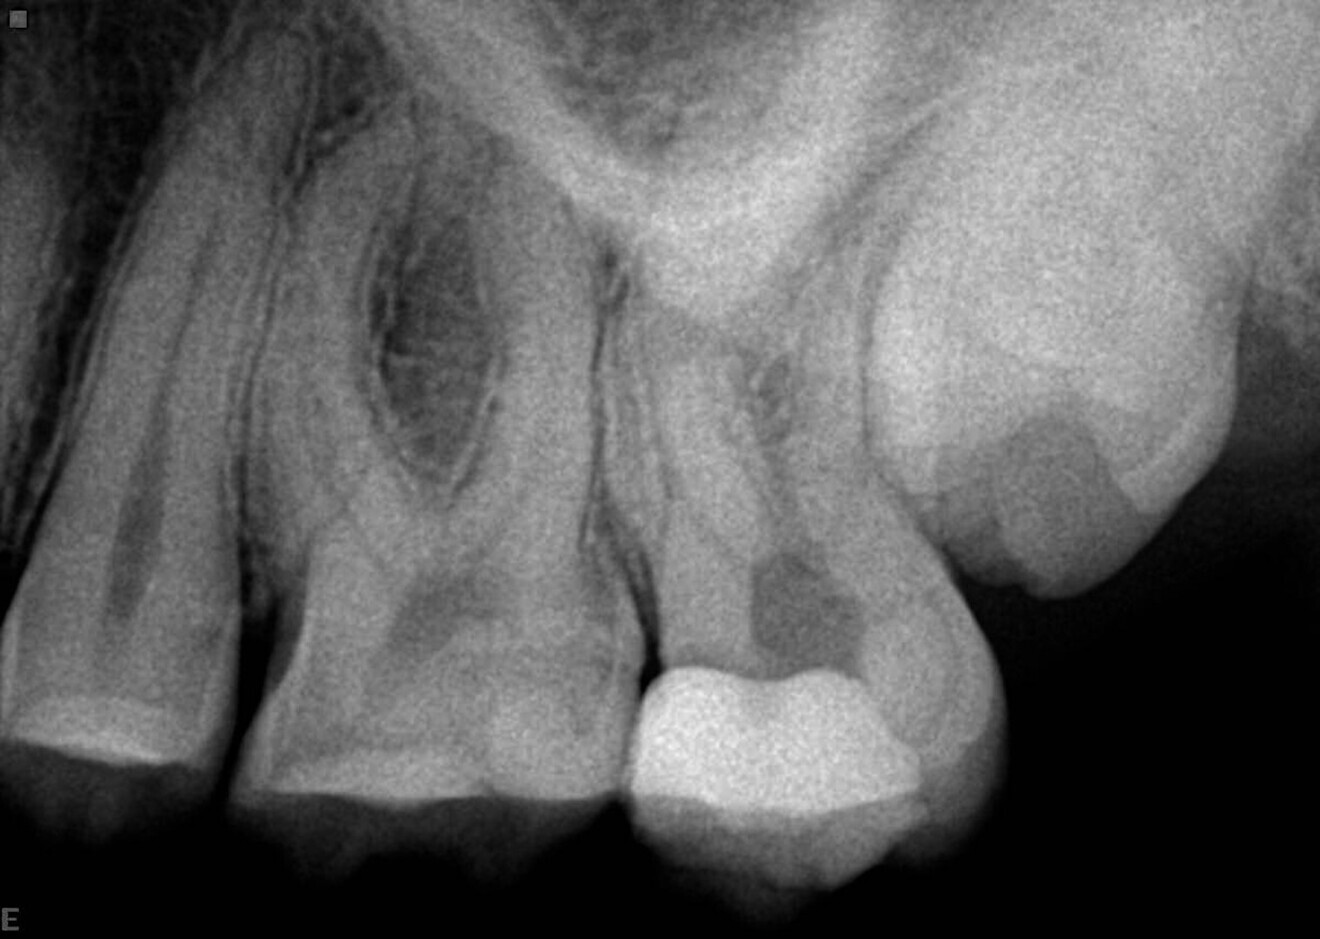

In this example case, the patient was referred by his treating dentist, who had penetrated deep into the roots in trying to find the canals and was not successful, but fortunately no perforation had occurred (Fig. 8). Under the microscope and using ultrasonic tips, the canals were made accessible. On the radiograph, we can see that the canals, especially the mesial ones, are narrow and have small curves, particularly apically. The real challenge in this case was maintaining the original shape of the canal. For those reasons, the sequence with the 0.04 taper was chosen. Treatment was initiated with the 25/0.08 Traverse orifice opener, followed by a 8 K-File for working length determination. The 13/0.06 Traverse file was used all the way to the end of the working length, followed by the 20/0.04 and 25/0.04 ZenFlex files, both taken to working length. For apical enlargement, the 30/0.04 ZenFlex file was used.

A medium cone was used as the master cone in the distal root, and fine-medium cones were used in the mesial root. A full sequence of irrigation was used during the treatment, and the system, which included a deep isthmus between the mesial roots, was filled in multiple levels from the middle to the apex, achieving beautiful 3D obturation (Fig. 9).

Fig. 8

Fig. 9